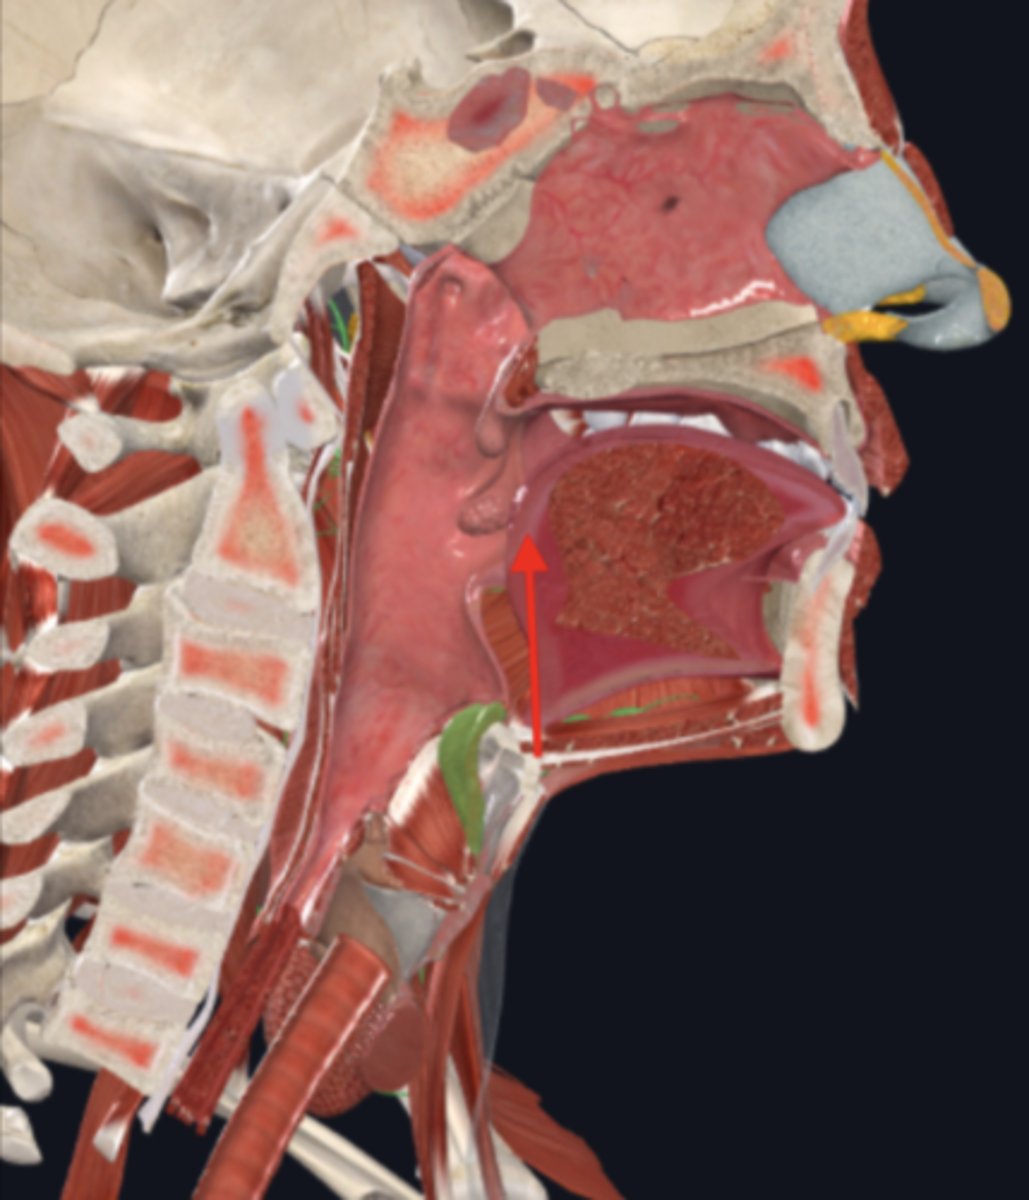

nasopharynx

name the circled region

oropharynx

name the circled region

laryngopharynx

name the circled region

epiglottis